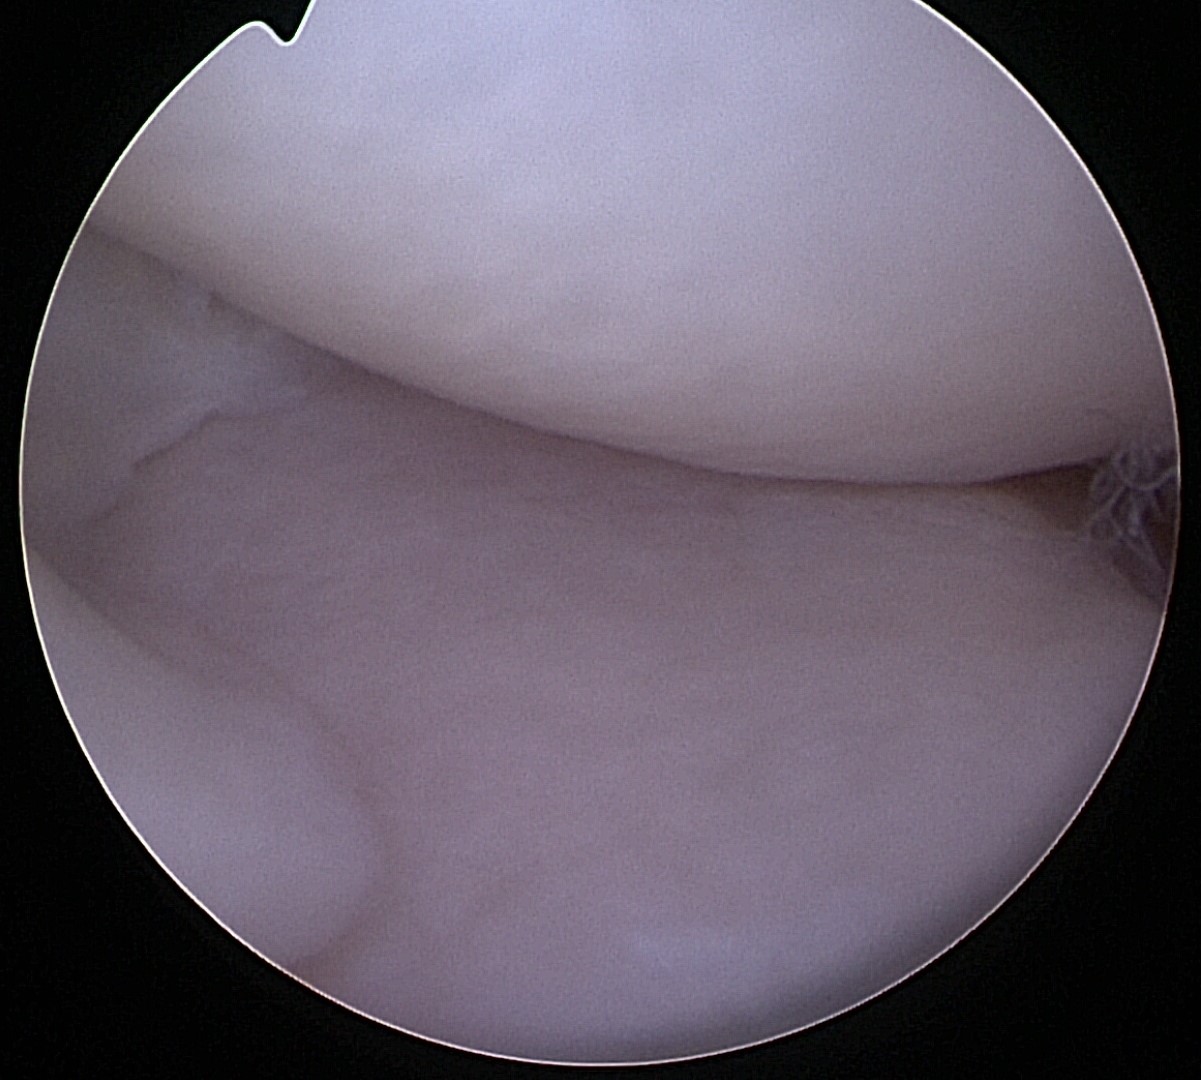

Normal Dog Meniscus

There are two menisci (the medial meniscus and the lateral meniscus) in each dog knee that serves as cartilage cushions or shock absorbers.

Due to this shock absorbing effect, a healthy canine meniscus helps prevent the dog’s knee joint from wear and tear. In dogs with CCL injuries, the medial meniscus is often affected, while the lateral meniscus is rarely torn. Proper treatment of dog meniscus injuries following a CCL rupture includes thoroughly evaluating the menisci to ensure there is no tear.

Arthroscopy is one of the best methods to assess dog knee injuries, offering a minimally invasive and accurate way to detect tears. If a canine meniscus tear is found during the arthroscopy, the damaged portion is removed or, in rare cases, repaired.

The following images and video demonstrate a normal canine medial meniscus.

Following removal of the torn portion of the canine meniscus the remaining meniscus can be seen (within the left side of the image to the bottom right) and the femur (in the upper portion of the image to the bottom right) can now comfortably rest on the tibia. Note that the cartilage in this dog’s knee is still in good health and removal of the meniscus does not equate to “bone on bone” contact.